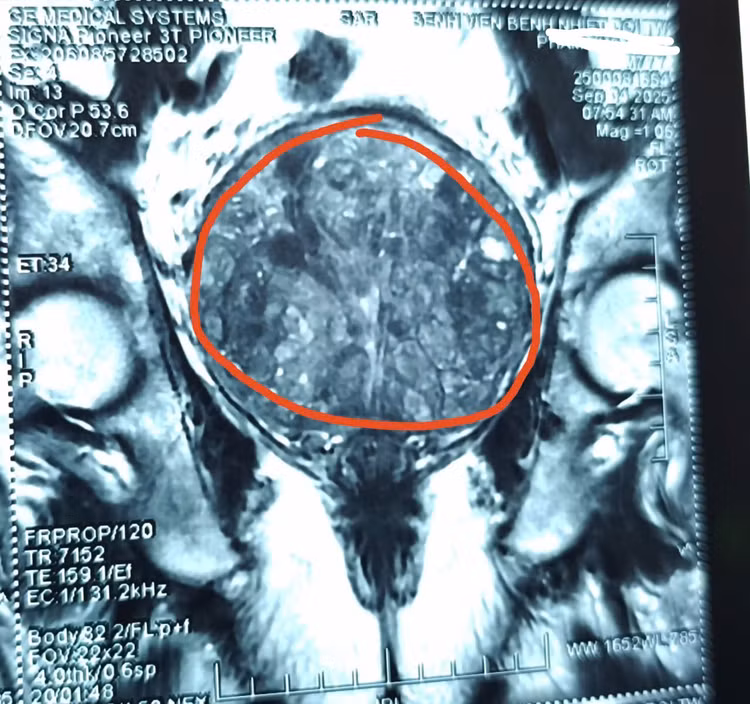

Tại Khoa Ngoại Tổng hợp, Tiết niệu và Nam học, ông S. nhập viện trong tình trạng tăng huyết áp, đái ra máu, nhiễm khuẩn tiết niệu nặng. Khám lâm sàng cho thấy tuyến tiền liệt phì đại bất thường, cùng với khối cứng ở tinh hoàn và mào tinh hoàn hai bên. Để kiểm soát nhiễm khuẩn, các bác sĩ phải rửa bàng quang liên tục bằng dung dịch Betadine.

tien-liet2.jpg

tien-liet-1.jpg

Khối u tuyến tiền liệt cho bệnh nhân - Ảnh BVCC

Theo BSCKII Trần Thượng Việt, Trưởng Khoa Ngoại Tổng hợp, Tiết niệu và Nam học, ông S. đã được chỉ định phẫu thuật tuyến tiền liệt từ lâu nhưng liên tục từ chối, ông chỉ muốn đặt ống thông tiểu để giảm triệu chứng.

Sau ca mổ cắt trĩ, ống thông tiểu gây chảy máu tại tuyến tiền liệt đã phì đại nghiêm trọng, nặng đến 484g – gấp hơn 20 lần kích thước bình thường (20-30g) và gấp 6 lần mức phì đại nặng thường gặp ở người trên 60 tuổi.